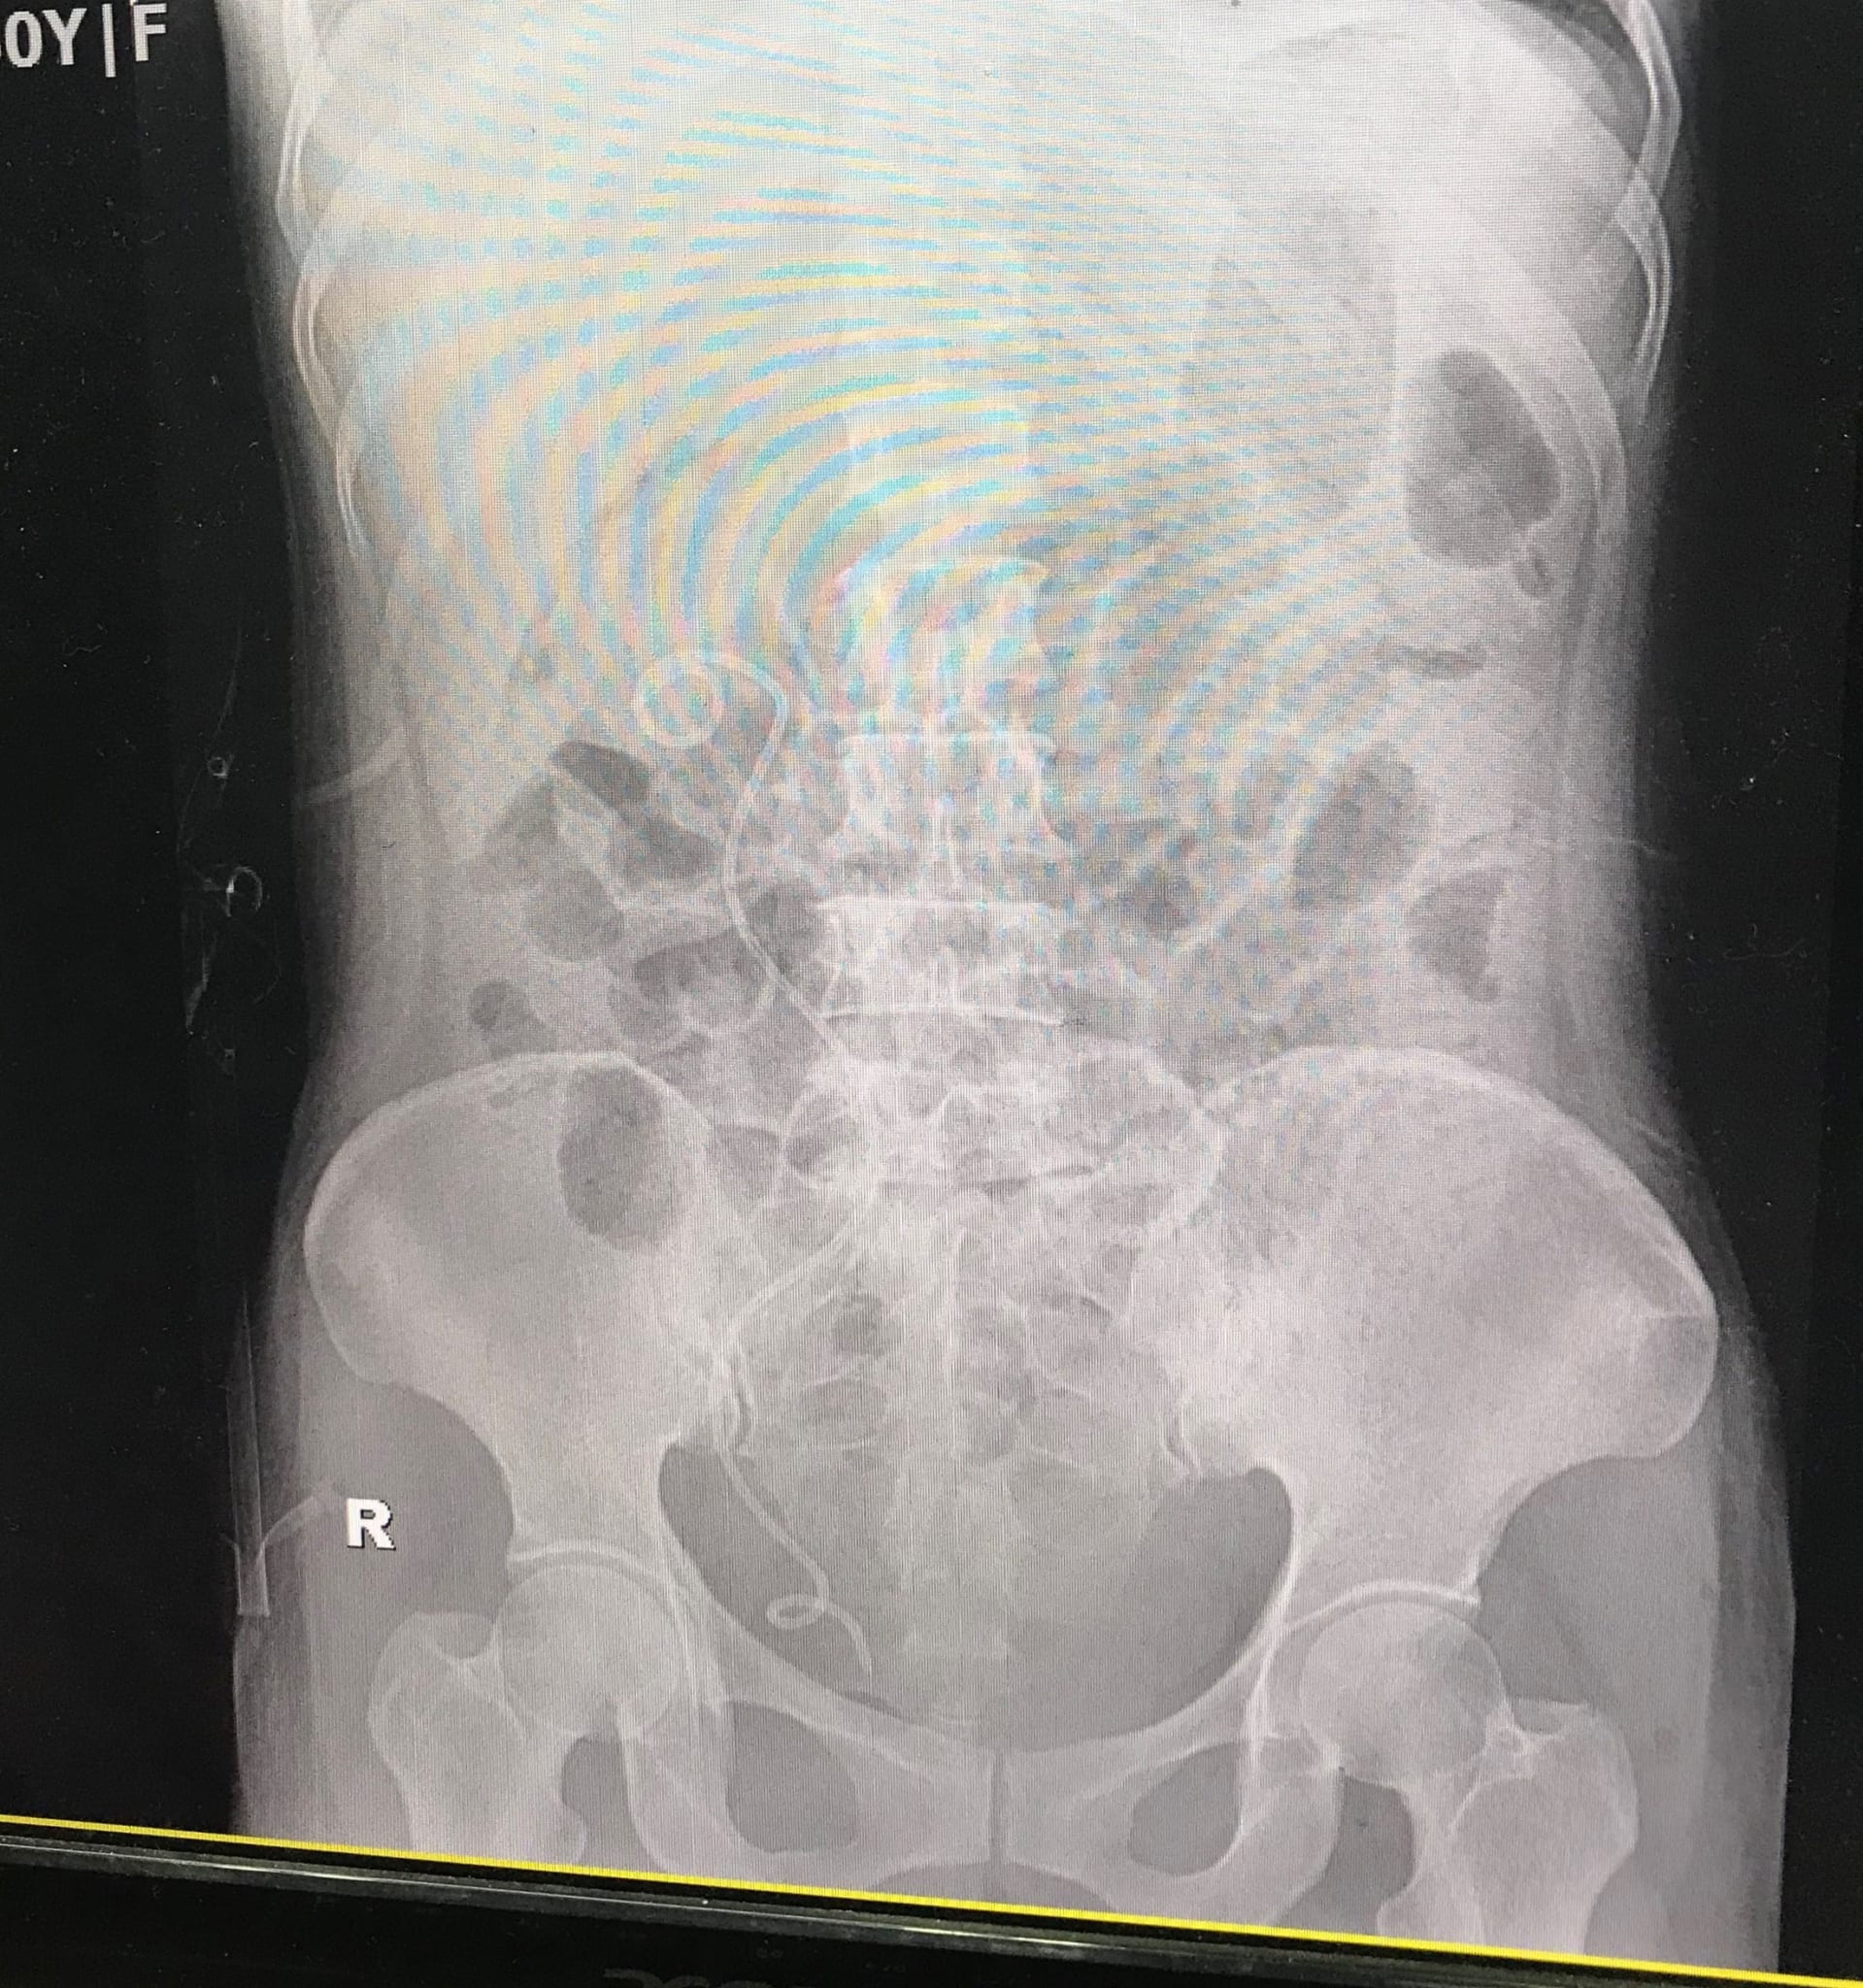

Bệnh nhân P.T.T, 50 tuổi, ở Tiên Lãng, Hải Phòng đau tức vùng thắt lưng 1 năm nay. Qua thăm khám và hình ảnh chụp Xquang, các bác sĩ tại Bệnh viện đa khoa Quốc tế Hải Phòng chẩn đoán người bệnh có sỏi san hô, kích thước 3cm và nhiều sỏi rải rác trong thận phải.

Quá trình thực hiện, các bác sĩ đã tiến hành rạch da khoảng 0,5cm vùng thắt lưng, tạo một đường hầm nhỏ từ ngoài da vào thận, đưa máy nội soi qua đường hầm tìm sỏi. Sau đó sử dụng tia Laser tán vỡ sỏi thành từng mảnh nhỏ và hút các mảnh sỏi vỡ này ra ngoài qua đường hầm. Kết quả kiểm tra sau mổ, sỏi đã được tán hết, trong thận không còn sỏi và bệnh nhân được hẹn tái khám sau 1 tháng.